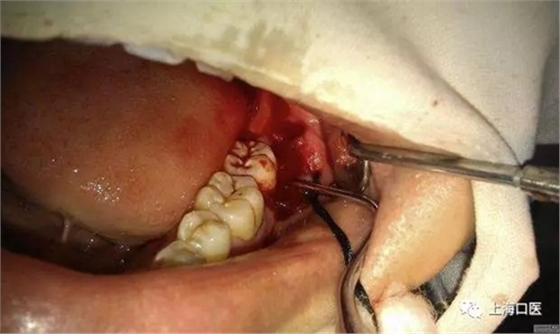

智齒拔除

口腔照

分牙

縫合

拔除后的智齒

我們拔牙時(shí),能不用錘就不用,盡量減少創(chuàng)口,用錘分牙去阻的干槽癥發(fā)生率遠(yuǎn)大于用手機(jī)分牙去阻的發(fā)生率,所用要多用手機(jī),少用錘,用手機(jī)的時(shí)候也要注意,保護(hù)好牙周的軟組織,還有一點(diǎn)就是在分牙前一定要把手機(jī)中的潤(rùn)滑油噴干凈,至少要讓手機(jī)先轉(zhuǎn)三分鐘,在很多拔牙術(shù)后,發(fā)生不明原因的疼痛,在一定程度上和手機(jī)殘留潤(rùn)滑油有關(guān),值得斟酌,且不管是否有關(guān),只要我們做了工作,做好了細(xì)節(jié),自然可以減少患者疼痛的發(fā)生率的。細(xì)節(jié)決定成敗,一定要做好每一步工作,才能越趨于完美。